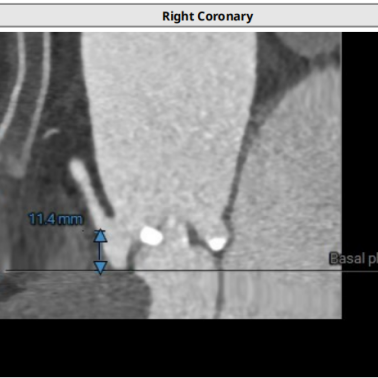

术前CT评估

● type1型二叶式主动脉瓣,L-R窦融合嵴,瓣叶明显增厚伴重度钙化;LVOT呈收口形;

● 左右冠脉开口高度尚可,切线位左右冠瓣叶长度>冠脉开口到瓣叶附着缘距离;

● 瓦氏窦、窦管交界内径正常,升主动脉扩张;

● 瓣环平面与水平夹角为55°,近横位心,主动脉弓夹角、弓距尚可;

● 腹主动脉散在钙化点,血管未见迂曲,入路血管直径良好。

主动脉根部测量

瓣上结构测量

冠脉阻挡风险、左室大小及横位心评估

外周血管入路评估